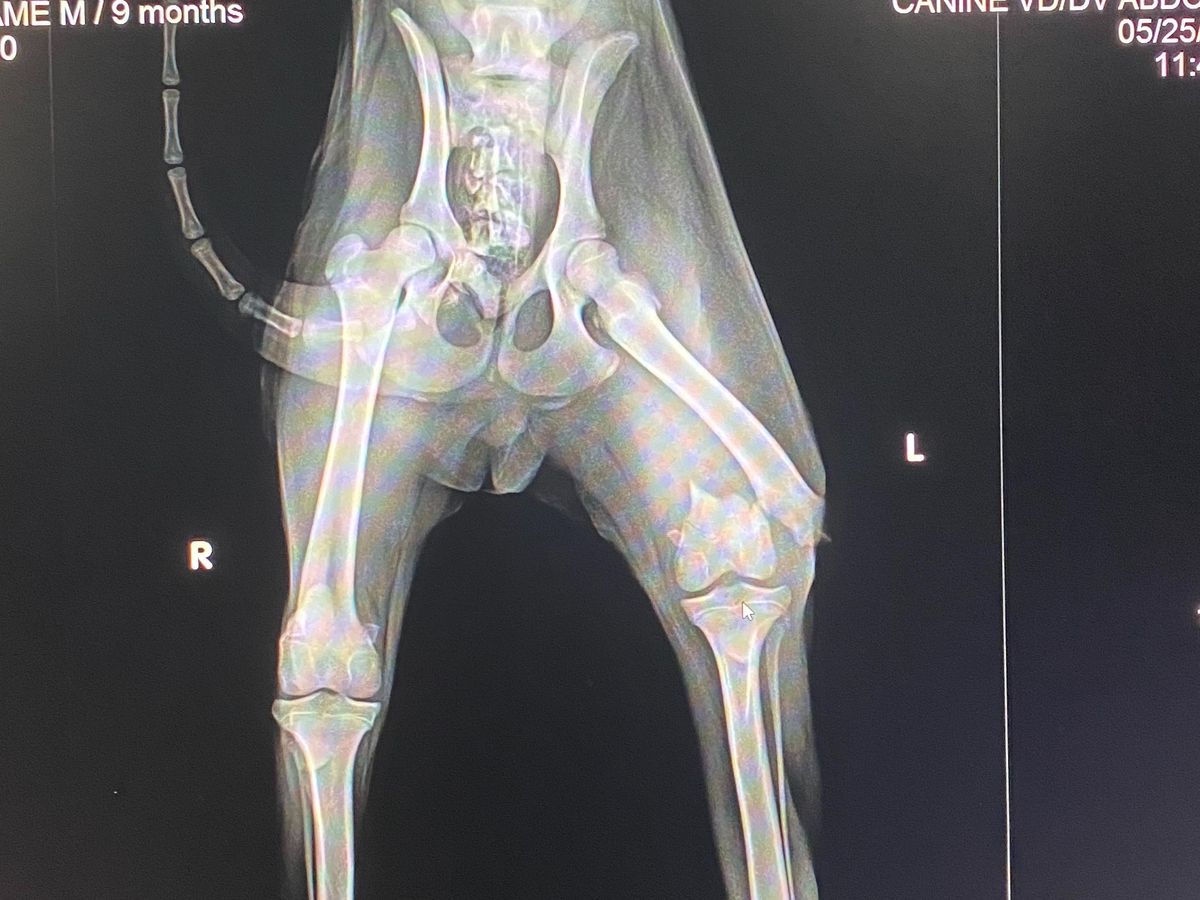

I found a stray, limping dog on Sunday and I was informed by the vet that his leg will need surgery because it’s broken or an amputation. I am 16 and can’t pay for him so I’m asking you to donate and help him have a wonderful, full life.